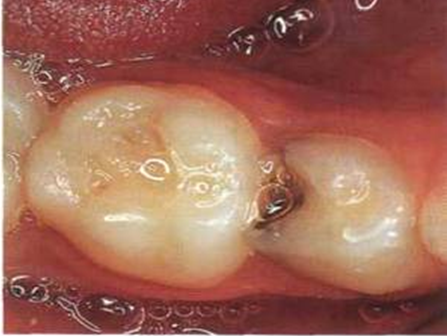

Danas postoje metode jednostavnog zaustavljanja uznapredovalog karijesa bez preparacije (“bušenja”) pomoću preparata srebra i fluorida, uz jedinu manu da tretirana lezija ostaje crne boje. (Slika 4). Detaljnije